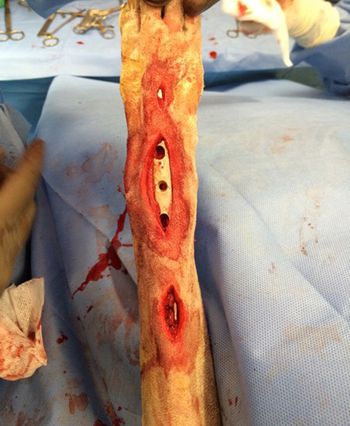

We all know orthopedic surgery and fracture repair is sexy, but does that mean you should be performing it? Veterinary surgeon Dr. David Dycus addresses this question, and more.For the average general practitioner, performing complex fracture repairs lives in the realm of referrals. Whether you repair or refer, there are important rules and new techniques that David Dycus, DVM, MS, CCRP, DACVS (small animal), wants you to know.Fracture repair is NOT typically an emergency surgery